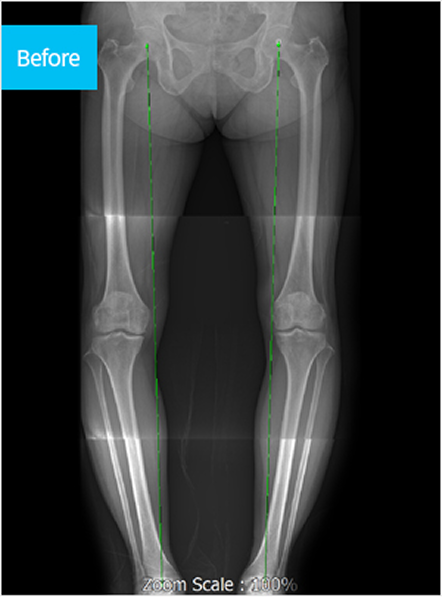

근위경골 절골술이란?

근위경골 절골술은 퇴행성 관절염 환자 중 인공관절 수술을 하기에는

이른 나이인 60세 이하의 환자들에게 주로 시행하는 치료법입니다.

환자 자신의 관절을 최대한 보존하면서 정렬을 교정하기 때문에

운동 기능이 유지되고, 외관상 휜 다리도 개선되어 만족도가 높은 치료법입니다.

좌식 생활이 많은 우리나라에서는 무릎 관절염 환자에게 O자형 변형이 자주 나타나는데,

이는 무릎 관절을 이루는 연골, 뼈, 인대 등이 특히 내측에서 손상되기 때문입니다.

이러한 내반변형이 한 번 발생하면 이후 지속적으로 악화되어 내측에 집중된 변형이 진행됩니다.

절골술을 시행하여 휜 다리를 교정, 정상 각도를 유지